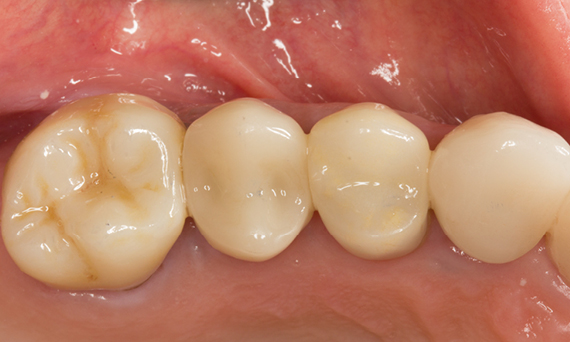

Before: Large insufficiency of the composite filling on tooth 16 with distal marginal ridge cracks, a lingual wall crack and distal recurrent decay.

After: Highly esthetic full-surface glass-ceramic crown.